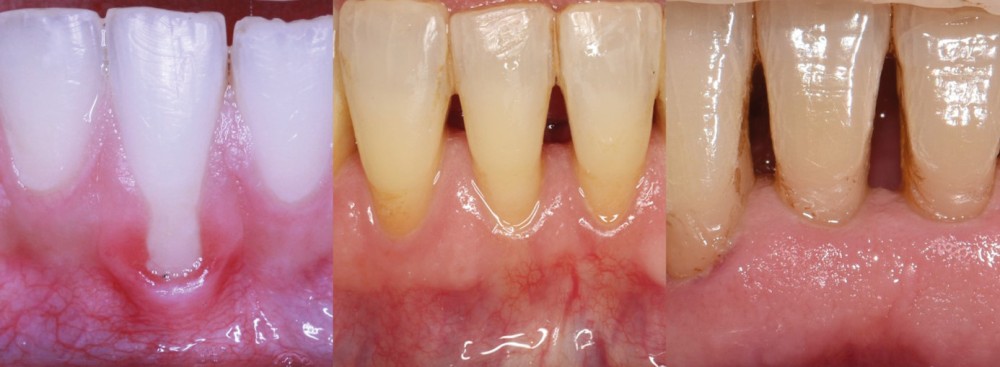

Concernant la terminologie, la classification de Cairo [6] détaille le type de récession.

La récession RT1 est une récession sans perte d’attache interproximale et où la JAC est cliniquement non détectable en zone interproximale, le recouvrement complet est possible. Lorsque la perte d’attache interproximale est inférieure ou égale à la perte d’attache vestibulaire, on parlera de récessions RT2, le recouvrement ne sera que partiel. La récession RT3 est une récession où la perte d’attache interproximale est supérieure à la perte d’attache vestibulaire, dans ce cas-là le recouvrement est impossible. Il est important aussi de savoir identifier et distinguer la récession gingivale de l’éruption passive incomplète qui est une anomalie de développement de l’éruption dentaire (fig. 1).